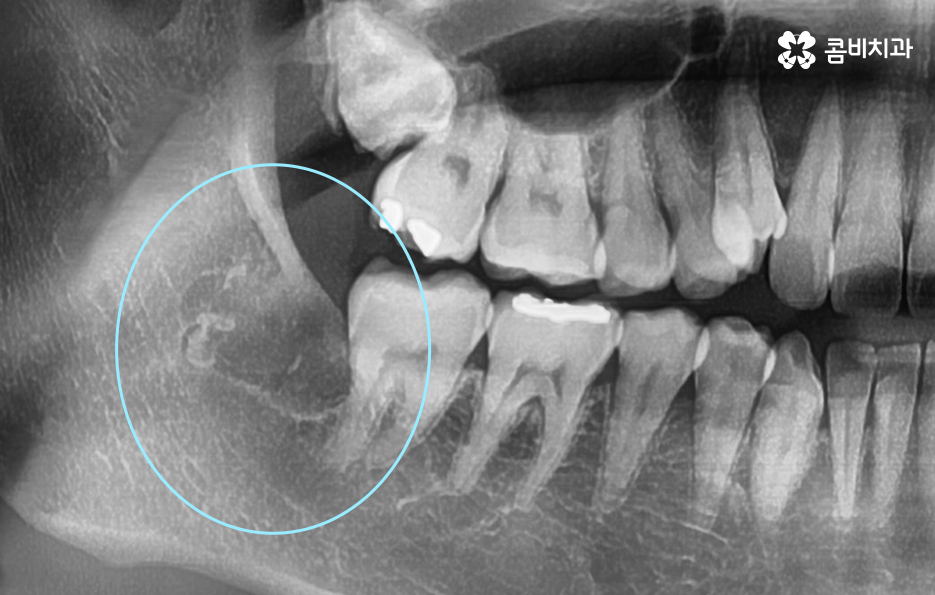

저작 기능에서 주된 역할도 하지만 위 사진을 다시 보시면 사랑니가 부분 매복되어 있는 상태로 누워서 자라고 있기 때문에 사랑니와 어금니 인접면에서 청결 관리가 잘 안되는 문제로 충치나 치주질환을 앓고 계신 분들도 많기 때문에 사랑니로 인해 어금니 문제가 발생하는 경우도 많이 있어요

다시 위 어금니 사진을 살펴보면 사랑니가 매복되어 있긴 하지만 위쪽 부분이 살짝 잇몸 밖으로 드러나 있는 것을 볼 수 있는데요. 평소 칫솔질을 잘하더라도 사랑니로 인해 청결관리에 미흡한 점이 생기면 주변 치아에도 충치가 전염되는 등의 안좋은 영향을 주는 경우가 많으며 부분 매복 사랑니의 경우 충치가 아니더라도 잇몸 염증의 주된 원인이 되고 있기 때문에 발치하는 것을 각종 구강질환을 예방하기 위해 권하고 있어요

오늘 케이스 사진의 경우 사실상 사랑니 하나만 보더라도 주변 치아에 충치 및 치주질환을 일으키기 쉬운 사례이며 누운 사랑니로 인해서 어금니의 씹는면 만이 아니라 인접면 충치나 손상으로 이어지기 사례로도 볼 수 있는데요